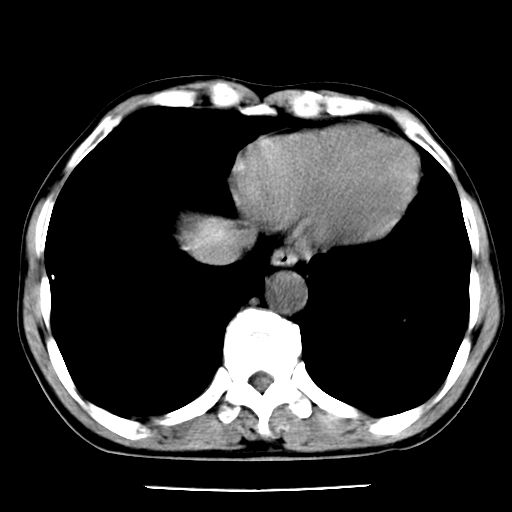

男,59岁,“结核性胸膜炎”30余年,胸部经常疼痛,多次x检查提示“肺部”炎症。腹部疼痛5日,b超提示:“肝内短管结石,余显示不清,建议进一步检查。”

两肺结核并右侧胸腔积液;脾脏、腹腔及腹膜后淋巴结结核[陈旧性];肝内胆管结石

胸部腹部都是结核(双肺。纵隔淋巴结,肝脏,脾脏,肠系膜)

两肺结核并右侧胸腔积液;脾脏、腹腔及腹膜后淋巴结结核[陈旧性];肝内胆管结石。直肠息肉?